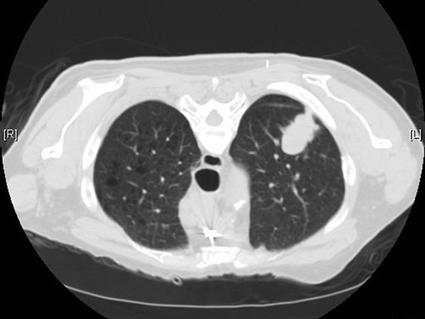

Imaging scans showing a lung nodule in panels A and B that enlarged over 11 months (panels C and D) and later confirmed as lung cancer via biopsy.

Imaging scans identified a lung nodule (panels A and B) which, over the course of 11 months progressed (panels C and D) and, following a biopsy, was confirmed as lung cancer.